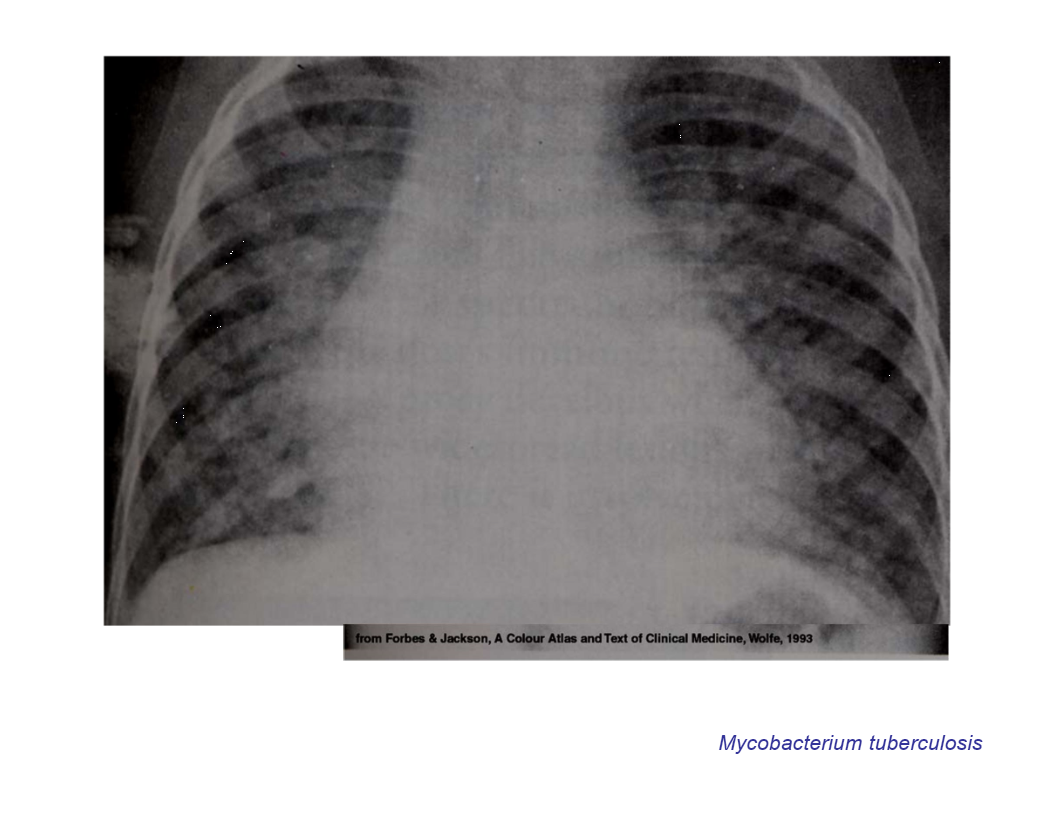

Miliart TB

widely disseminated TB not controlled by the immune system

may follow primary or reactivation tuberculosis

cough may or may not be present

hepatomegaly, splenomegal, and lymphadenopathy are common

frequently, CXR reveals a miliary reticulonodular (snowstorm) pattern

sputum AFB smears are usually negative

skin PPD testis negative in approximately 1/2 of cases